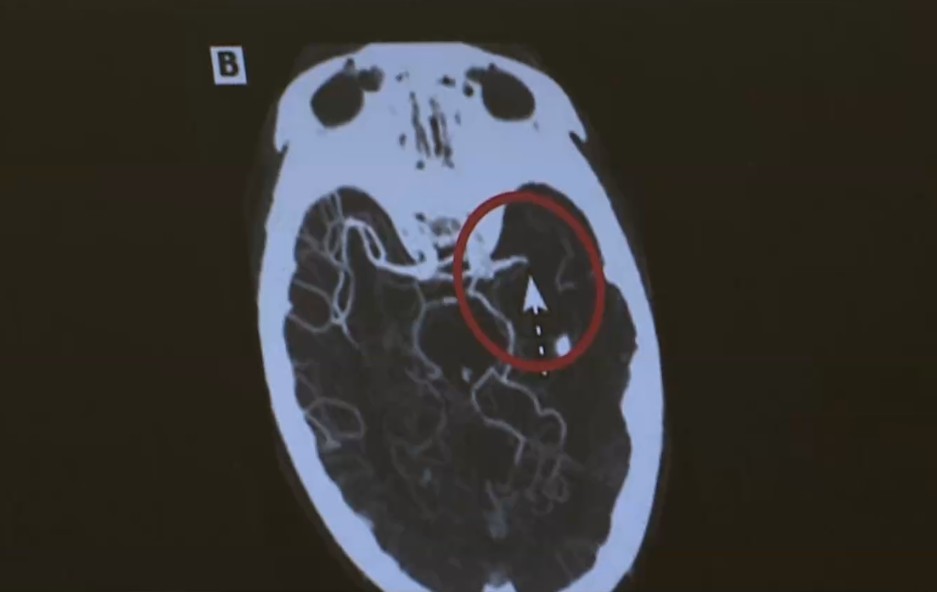

O Acidente Vascular Cerebral (AVC) é um grave problema de saúde que pode levar à morte. No Brasil, cerca de 90% dos casos estão associados a fatores de risco como hipertensão, diabetes e tabagismo. Por isso, manter uma rotina com bons hábitos de saúde é a melhor forma de prevenção.

Popularmente conhecido como derrame — é uma das principais causas de incapacidade no mundo. No Brasil, a maioria dos casos está relacionada a fatores de risco como hipertensão, diabetes, tabagismo, sedentarismo e consumo frequente de álcool.

De acordo com o médico neurologista Mateus Felipe dos Santos, adotar hábitos saudáveis é essencial tanto para prevenir o AVC quanto para se recuperar dele. Ele explica que estar atento aos sinais é fundamental para garantir um diagnóstico rápido e aumentar as chances de um bom resultado no tratamento. Principais sinais do AVC: Fraqueza ou dormência em um lado do corpo; Dificuldade para falar ou compreender; Alterações na visão; Tontura; Perda de equilíbrio ou coordenação; E dor de cabeça intensa e repentina.